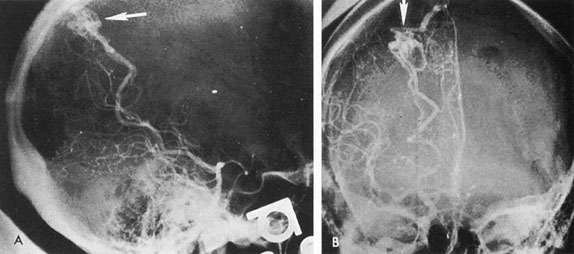

Vertebrobasilar System

Tortuous or redundant basilar arteries are not uncommon in the older age group. Occasionally, gross dilation or ectasia develops so that the basilar artery acts as a mass in the posterior fossa. This phenomenon produces signs of low-pressure hydrocephalus, cranial nerve palsies, and long tract and sensory signs and may even simulate a cerebellopontine angle tumor or tumor at the foramen magnum.58 It is possible to diagnose such lesions with CT59 or MRI60 but angiography is definitive (Fig. 6). The association of insidious multiple cranial nerve palsies and long tract signs referable to a brainstem level, in an elderly patient with evidence of atherosclerosis, should make fusiform basilar artery dilation a diagnostic consideration.

Fig. 6. Fusiform basilar dilation. A: Lateral projection vertebral arteriogram showing a widened basilar artery (arrow) projecting beyond level of dorsum sellae. B: Anteroposterior projection showing a widened and tortuous basilar artery.

As opposed to saccular basilar aneurysms, fusiform aneurysms tend to occur in the older age group (older than 60 years) and are found predominately in men.2,36 They are commonly associated with hypertension and atherosclerotic cardiovascular disease, and a notable association with abdominal aortic aneurysms also exists.